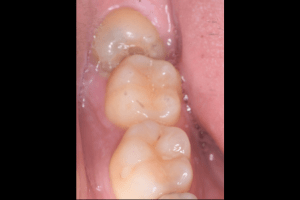

右上下の親知らず抜歯症例

- 右上抜歯前の写真

- 右上抜歯後の写真

- 右下抜歯前の写真

- 右下抜歯後の写真

| 抜歯内容 | 右上8番普通抜歯 右下8番の半埋伏抜歯 |

| 治療方針 | 右上8番と上顎洞との位置関係と、右下8番と神経の位置関係を確認するためにCT撮影を行いました。 右下8番は半埋伏なので歯ぐきを切開後、骨を切削したり、歯を分割して抜歯しています。 切開した歯ぐきの箇所は2箇所縫合し、後日抜糸しています。 右上8番は切開することなく抜歯しました。 |

| 特記事項 | 右下8番は切開したところのみ縫合しています。 元々歯が出ていたところは穴が開いた状態になりますが歯ぐきが治るとともに穴も塞がります。 |

| 担当者所見 | 上下どちらとも歯ブラシが届かず、汚れが溜まっている状態で虫歯になったと思われます。 抜歯した歯の手前にある右上下7番の後ろ側が虫歯になり始めている状態でしたので、抜歯後もセルフケアが大切になります。 |